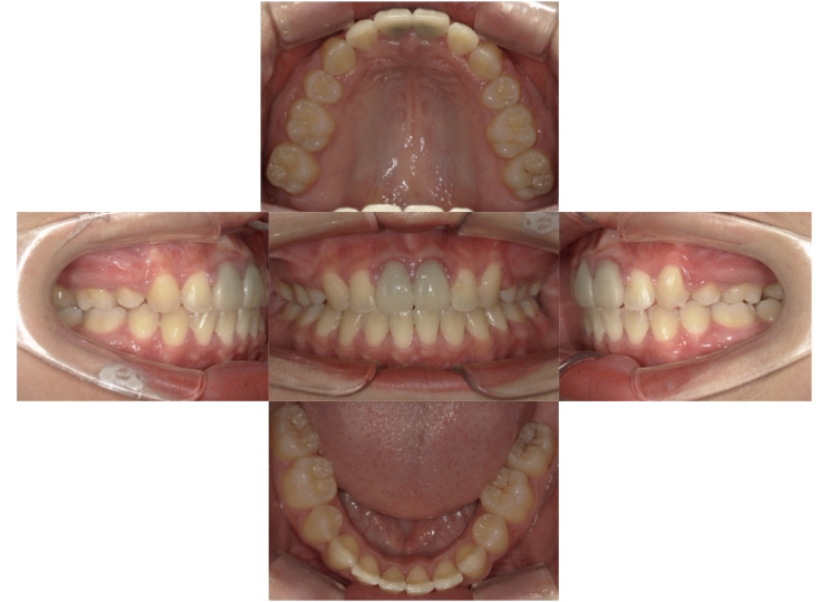

BEFORE

治療経過

AFTER